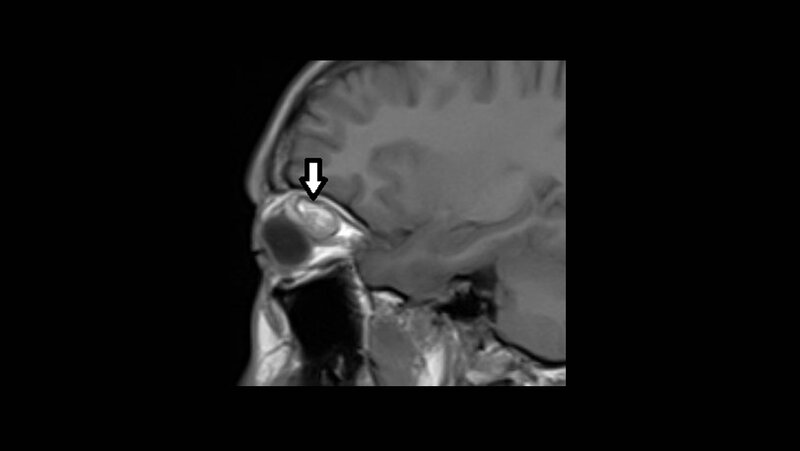

Vaskuläre Anomalien sind eine diagnostische und therapeutische Herausforderung. Isolierte venöse Malformationen kommen unter den intraorbitalen Gefäßanomalien am häufigsten vor, gefolgt von den lymphatischen und arteriovenösen. Die klinische Symptomatik kann visuelle oder okulomotorische Störung, Schmerz, Ptosis oder akute Blutung sein.

Vascular anomalies are a diagnostic and therapeutic challenge. Isolated venous malformations are the most frequent among vascular malformations inside the orbita, also lymphatic and arteriovenous malformations. The clinical symptoms can be visual or oculomotor alteration, pain, ptosis or acute bleeding.